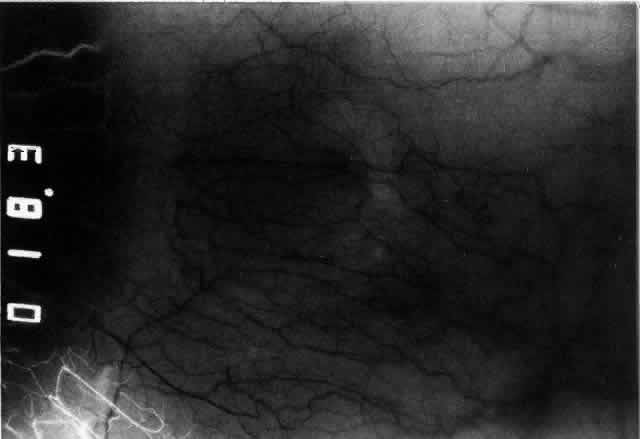

Fig. 23. Electron micrographs of scleral stroma at the periphery of an area of ulceration in a patient with necrotizing scleritis. The left shows an active fibroblastic cell, and the right shows collagen fibrils within intracellular vacuoles (V) in the fibroblastic cell. (Left X15,375; right X15,375) (Watson PG, Young RD: Changes at the periphery of a lesion necrotizing scleritis: Anterior segment fluorescein angiography correlated with electron microscopy. Br J Ophthalmol 68:781–789, 1984)

Fig. 24. Electron micrograph of scleral stroma at the periphery of an ulcer in necrotizing scleritis (same patient as in Figure 23) showing swelling and unraveling of collagen fibrils (arrows) in longitudinal section (X29,270) and in transverse section (inset, X44,000). Fibrils of all diameters are affected. (Watson PG, Young RD: Changes at the periphery of a lesion necrotizing scleritis: Anterior segment fluorescein angiography correlated with electron microscopy. Br J Ophthalmol 69:656–663, 1985)